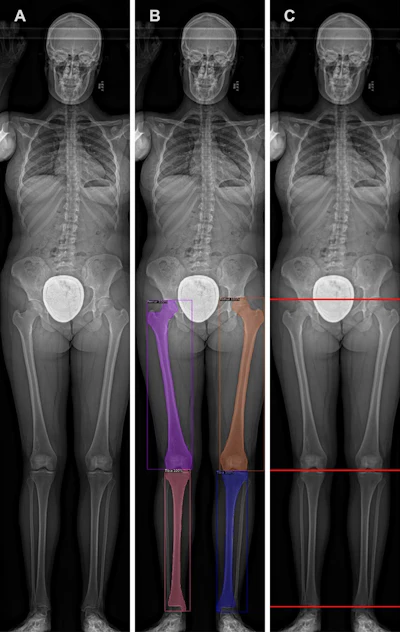

The lower extremity measurement pipeline is illustrated using a representative slot-scanning radiograph. The AI model was trained to segment the femur and tibia: (A) the original radiograph and (B) the same radiograph showing the segmentations (boxes) produced by the model. (C) The segmentations in B were used by the model to identify the top of the femoral head, medial tibial condyle, and tibial plafond (lines). These locations were used by the model to measure the length of the femur, tibia, and lower extremity overall. Image courtesy of Radiology.

The lower extremity measurement pipeline is illustrated using a representative slot-scanning radiograph. The AI model was trained to segment the femur and tibia: (A) the original radiograph and (B) the same radiograph showing the segmentations (boxes) produced by the model. (C) The segmentations in B were used by the model to identify the top of the femoral head, medial tibial condyle, and tibial plafond (lines). These locations were used by the model to measure the length of the femur, tibia, and lower extremity overall. Image courtesy of Radiology.

The CNN model was trained to segment the femur and tibia on the x-rays and measure total leg, femoral, and tibial length, with results showing the model’s mean absolute error measurements were 0.25 cm for the femur, 0.27 cm for the tibia, and 0.33 cm for composite lower limbs.